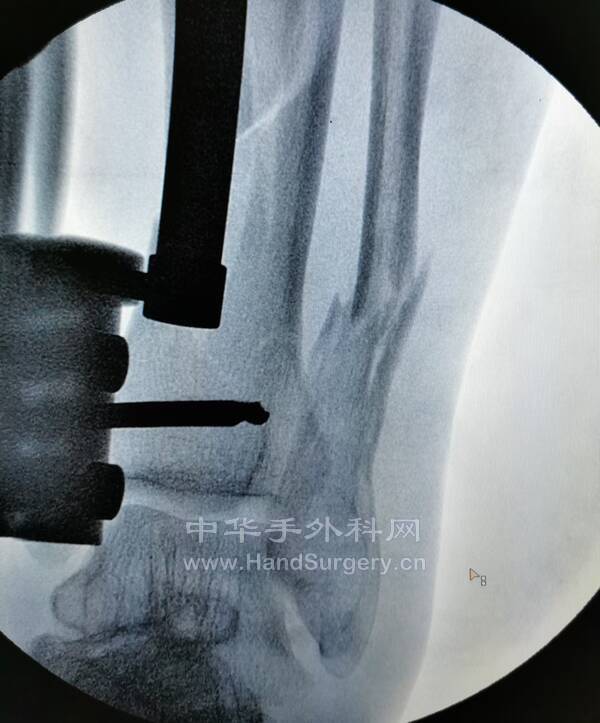

桡骨远端骨折,远端粉碎或太短,不能接受钢板远端钉排

克氏针+外固定支架是绝佳选择

这里就是其中一个典型病例

桡骨远端骨折C3型合并舟骨骨折

有限切开,外固定架的持续牵引,可以利用软组织夹板作用,维持粉碎骨块的复位